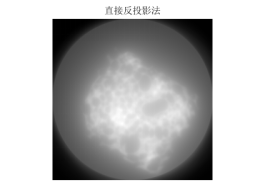

3.算法说明:本文用matlab进行算法实现,由于所给数据一列为一次扫描一列512个数180列,将题中所给的512180接受的数据进行拆分,将一列作为一个投影层。首先,将一列进行复制将第i列变成一个512512的矩阵,该矩阵没一列都是由第i列复制来的,由此可以得到180个矩阵,将第i+1个矩阵旋转1度加到第i个矩阵上,知道加完180个,然后除以射线条数,得到的512512的矩阵为所要成像图形的灰度像素矩阵,然后进行等比例缩小成体重要求的256256大小可得。程序见附录程序三,第一问结果如图九,第二问结果如图十,第三问结果如图十一.

图 9

图 10

图 11

由滤波公式与原来灰度像素矩阵每一列进行卷积,得到了消除边缘失锐的灰度像素矩阵再用原本未滤波的模型进行图形重建运算,程序见附录程序四,结果以及效果如下:

图 14

图 15

图 16